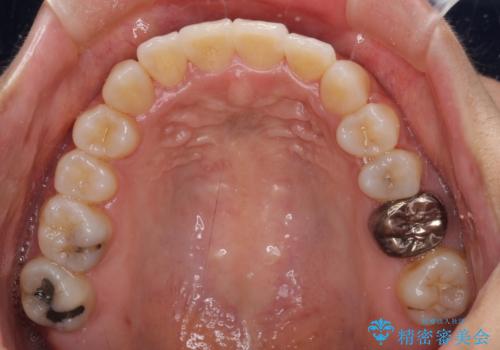

上顎骨の横幅が狭く、歯列が混み合っていたため、急速拡大装置により側方拡大し、咬み合わせと歯列を改善することとしました。

骨格的な問題を解決したことで、下顎は部分矯正で対応することができました。